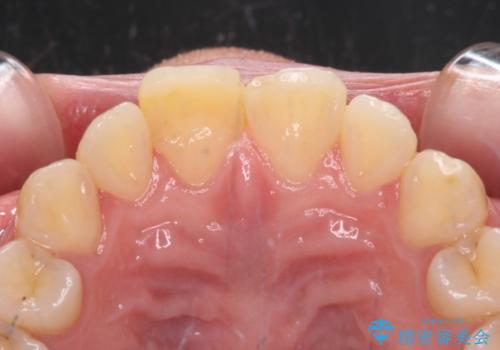

転んで欠けてしまった前歯 オーダーメイドのオールセラミッククラウン

転んだ際に歯の先端1/4ほどが欠けてしまい、近医にて修復をしてもらったとのことですが、将来的にオールセラミッククラウンを装着する可能性を説明されたため、当院にて補綴治療を行うこととしました。

オーダーメイドタイプのセラミッククラウンは、既製タイプのク色のラウン(スタンダードタイプ)とは異なり、色合いが合うまで何度も修正を行って調整をいたします。